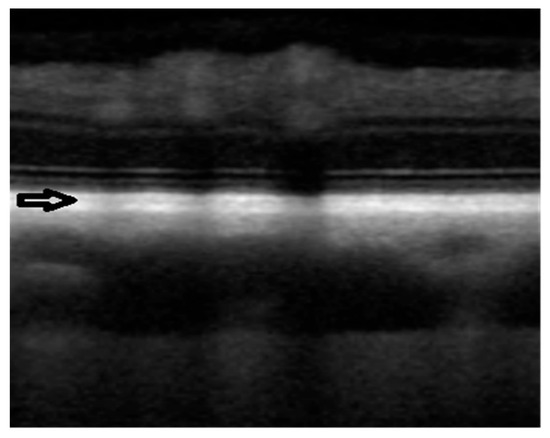

2.2. OCT Scan and Data Analysis